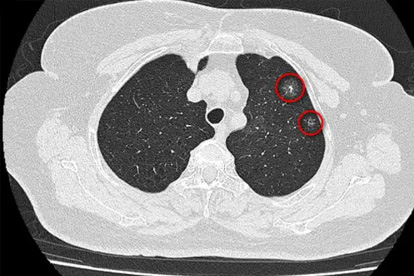

长期吸烟者、有肺癌家族史、长期接触二手烟或油烟、工作在粉尘环境的人群,出现上述任何症状都应尽早就诊。低剂量螺旋CT是目前筛查早期肺癌最有效的手段,高危人群建议每年检查一次。